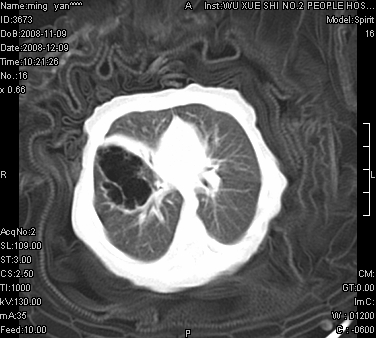

女.30天.咳嗽.喘3天.系三胞胎

考虑右肺下叶先天性肺囊肿,不除外合并右中叶肺发育不全

伴双肺感染

考虑右肺下叶先天性多发性肺囊肿可能。

考虑右肺下叶肺囊肿伴感染,右中叶节段实变或发育不全

这是一个先天性囊性腺瘤样畸形(congenital cystic adenomatid malformation,ccam),属于先天性肺发育异常,最近国外文献重新命名为先天性肺气道畸形(congenital pulmonary airway malformation,cpam),根据发生部位和畸形组织与气管、支气管的关系分成五型。本病以1岁以下婴儿多见,男性多于女性。病因为终末呼吸单元的异常增殖,形成多囊状结构。国内根据影响和病理表现分三型:ⅰ型为单个或多个大囊肿,直径大于2cm;ⅱ型为多个小囊肿,直径小于2cm;ⅲ型为大的非囊肿性病变,但显微镜下观察可见肿块由多发小囊组成(直径小于2mm)。本病可发生于肺内任何一部分,单侧肺占95%,中叶病变相对较少。